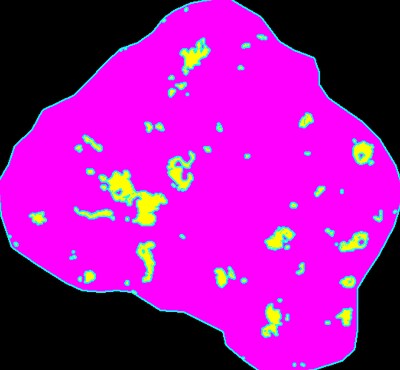

Ein Beispiel für die Analyse des Flächenverhältnisses des CD68 im Glomerulus ist unten dargestellt. Nachdem die HE-Färbung durchgeführt wurde, wurde eine Nierenbiopsie von oben betrachtet aufgenommen. Normalerweise ist es schwierig, das Bild zu fokussieren, wenn die Probe dick ist, aber die Z-Stapel-Bilderfassung ermöglicht, dass das gesamte Bild scharf abgebildet wird.

Glomerulus-Flächenverhältnis: 4,3%